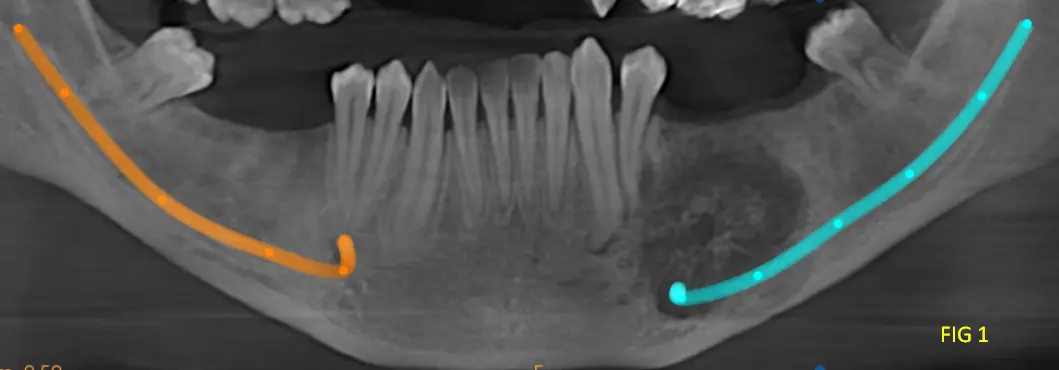

En las reconstrucciones 3D y cortes multiplanares (ver Fig 1, 2 y 3) se observa lesión oseteolítica extensa con ausencia de una capsula definida, ubicada en el cuerpo mandibular, lado izquierdo, zona de premolares.

Presenta tabiques óseos finos que delimitan compartimentos irregulares con expansión y adelgazamiento de las corticales óseas, con áreas de compromiso cortical. La relación cercana con el conducto dentario inferior, sin evidencia clara de invasión, pero con desplazamiento y borramiento en sectores de dicha pared del conducto.